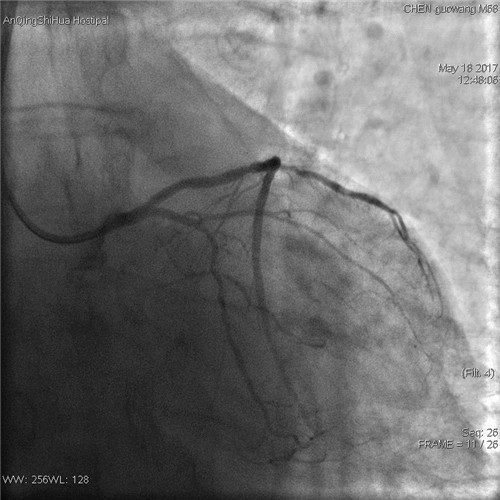

術(shù)后 回旋支血流通暢

術(shù)后 前降支支架內(nèi)狹窄解除